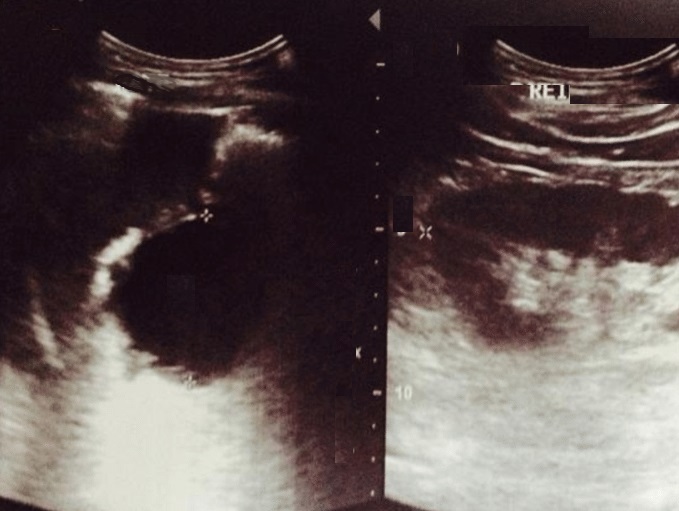

Image

echographique percutane abdominale d'une kyste

hydatique active type I du pancreas avec

aspect lesionnel de nodule ovalaire aechogene a

paroi lisse , bord nette regulier , situe au tete du

pancreas . |

En differencie avec aspect

lesionnel d'echographie d'une pseudokyste du

pancreas aechogene a limite nette regulier et n'a

pas de la paroie . cone de hyper ascoustique

posterique en vue nette |